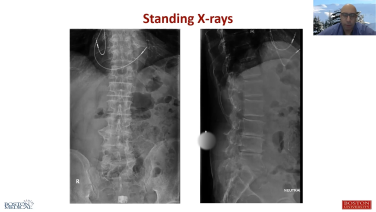

Anterior to Psoas Technique Case Presentation - Chadi Tannoury, MD